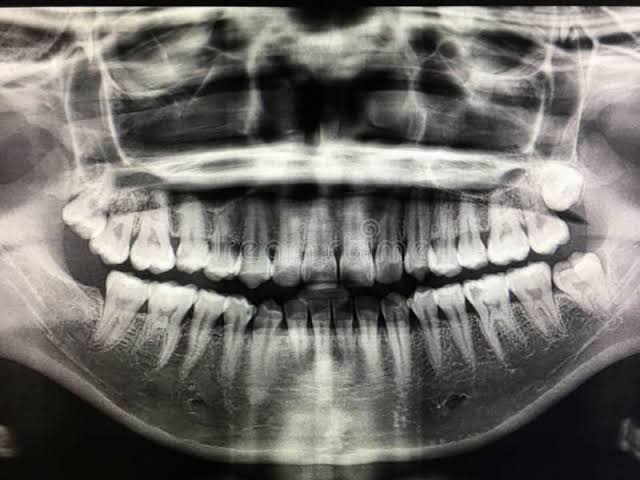

The image shows how many of the patient\’s teeth that are free of fillings?